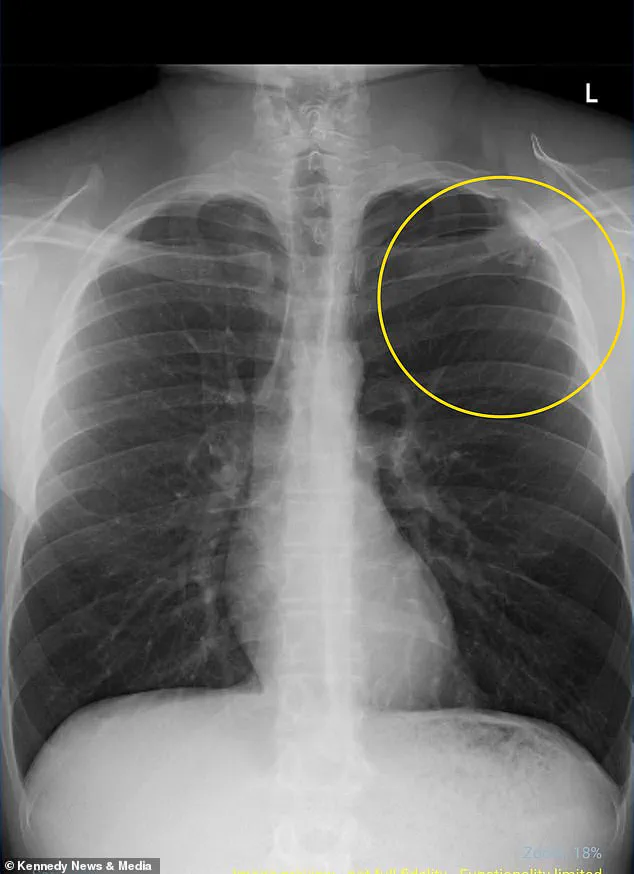

Rushed to the hospital, doctors diagnosed him with a partially collapsed lung, a condition medically termed pneumothorax.

This occurs when air leaks into the chest cavity, creating pressure that causes the lung to collapse.

An x-ray scan revealed that his left lung had collapsed by 10 percent, a minor collapse by medical standards, but one that required immediate intervention.